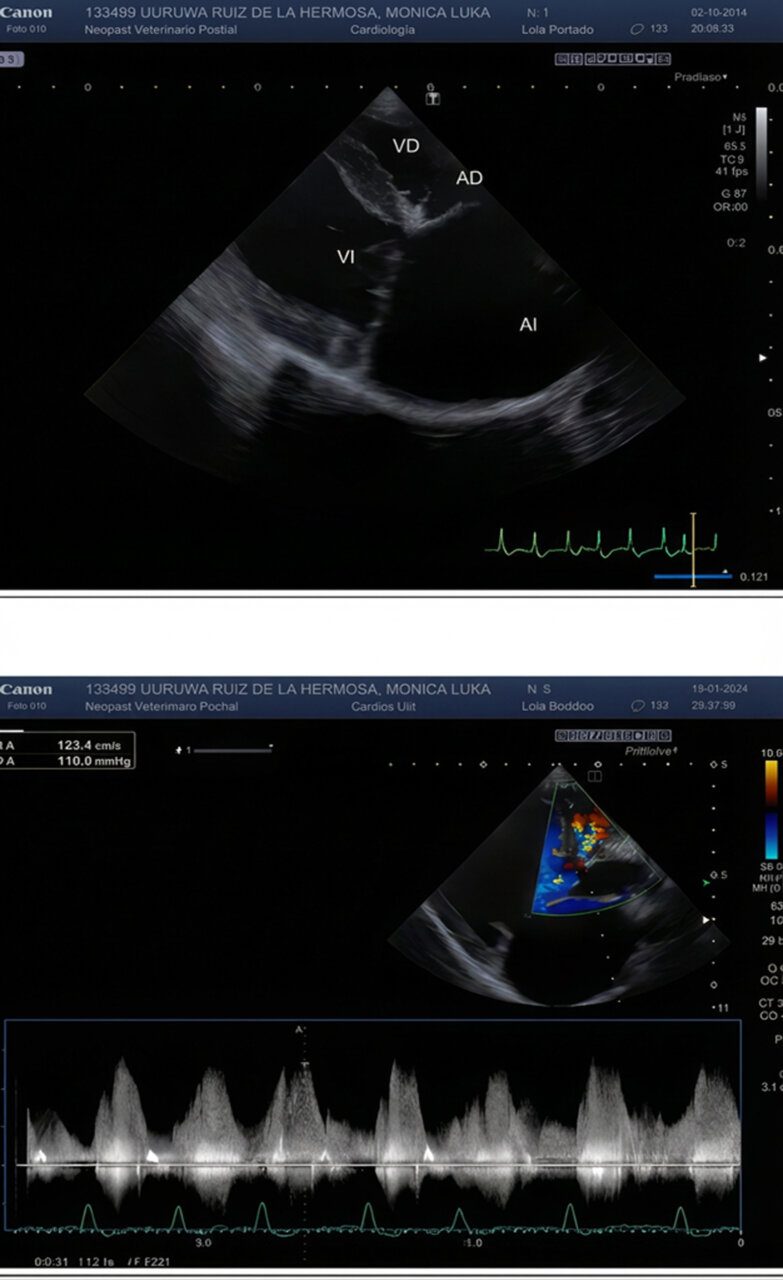

Antes de la planificación de la cirugía, se recomendó una revisión por parte del Servicio de Cardiología del centro para evaluar la gravedad de la patología cardiaca. Se realizó un estudio ecocardiográfico, que mostró la existencia de un defecto perimembranoso del septo interventricular y cuadricuspidía aórtica con grave remodelación atrioventricular izquierda y complicada con fibrilación atrial (FA) (imágenes 1 y 2). Se decidió mantener el tratamiento actual, con la excepción de la amiodarona, que se suspendió y sustituyó por diltiazem cada 12 horas y digoxina cada 12 horas para el tratamiento de la FA. También se añadió amlodipino cada 12 horas.

La duración total de la anestesia fue de 60 minutos y la de la cirugía, de 40 minutos. El electrocardiograma mostró un ritmo predominantemente de FA a 110-120 lpm, sin otras anomalías reseñables (imágenes 3 y 4). Tras la extubación, se administró meloxicam 0,2 mg/kg. El paciente se recuperó de forma lenta pero adecuada, sin que se observasen anomalías en la exploración física. Se mantuvo la oxigenoterapia por mascarilla en el posoperatorio temprano para evitar el riesgo de hipoxemia y se monitorizó la saturación de oxígeno mientras el paciente lo toleró. Fue dado de alta el mismo día por la tarde.